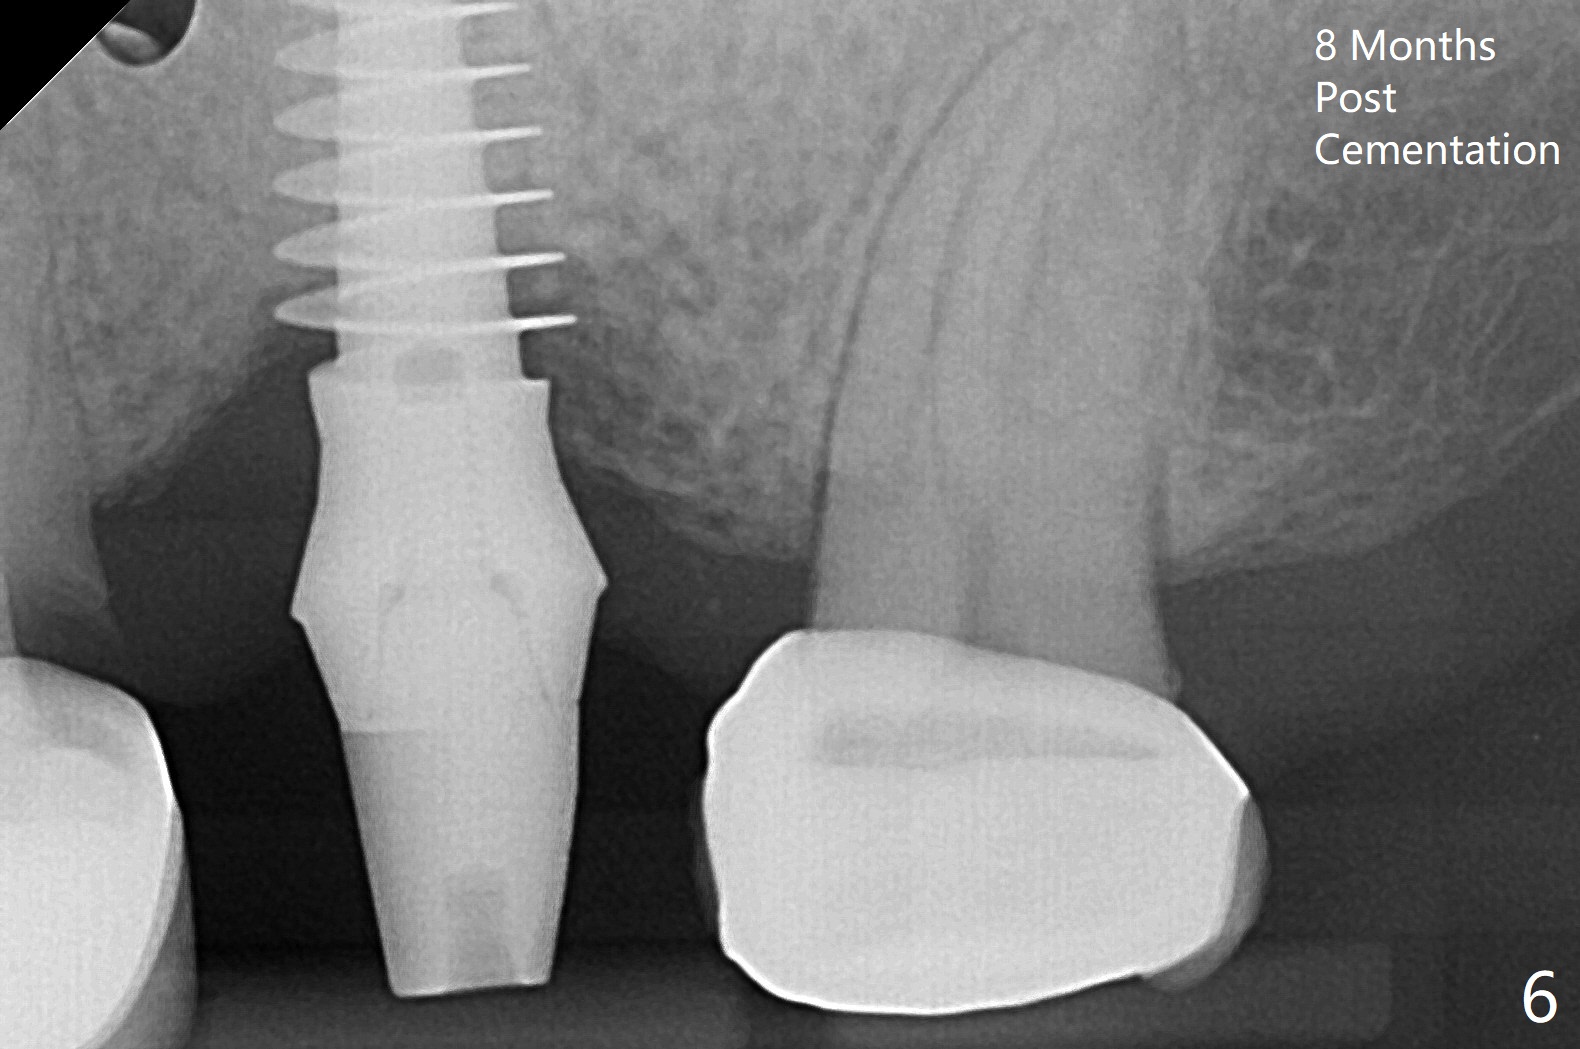

After 4.5x11.5 mm drill (10.5 mm offset) and 5.0 mm tap with guide at #14, the depth of the gingiva is measured 3 mm. A 5.5x9(3) mm Magicore cannot enter the green sleeve and is placed free hand (Fig.1). The margin is slight subgingival mesiodistal. With 3-4 turns, the buccal margin is slightly subgingival, while the palatal one slightly supragingival (Fig.2). The length of the implant could be 11 mm, considering the apical space (double arrows). To prevent periimplantitis, what is the appropriate placement depth coronally? Where does Titanium end? Dr. Wang thinks that the placement level is right. Probably due to underprep, the mesial crestal bone appears to have been resorbed 7 months postop (Fig.3 ^, as compared to Fig.1). The gingiva is healthy. A 4.3x5 mm solid abutment is torqued 20 Ncm for impression. The guide allows the implant to be placed lingual because of buccal concavity (Fig.4), but the coronal end of the solid abutment in the center for restoration (Fig.5 A). The crown is seated partially on the Magicore (M). The temp bond cemented crown is off 8 months post cementation (Fig.6). The bone density increases especially mesial.